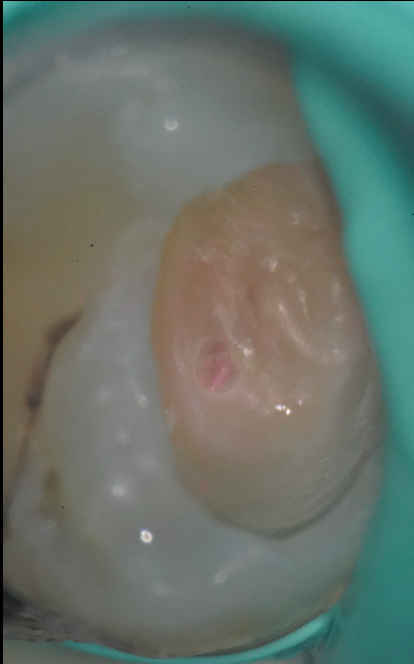

治療前

まずは虫歯検知液を使用して、虫歯に侵された部分(軟化象牙質)を染色します。

しかし、一度の染色ではすべてが把握できないことが多く、少しずつ削っては染色→確認という作業を何度も繰り返します。

軟化した象牙質は、よく切れるスプーンエキスカベーター(手用器具)で、触知しながら確認・除去します。

機械ではわかりづらい“手の感覚”で、感染の有無を確認する工程です。